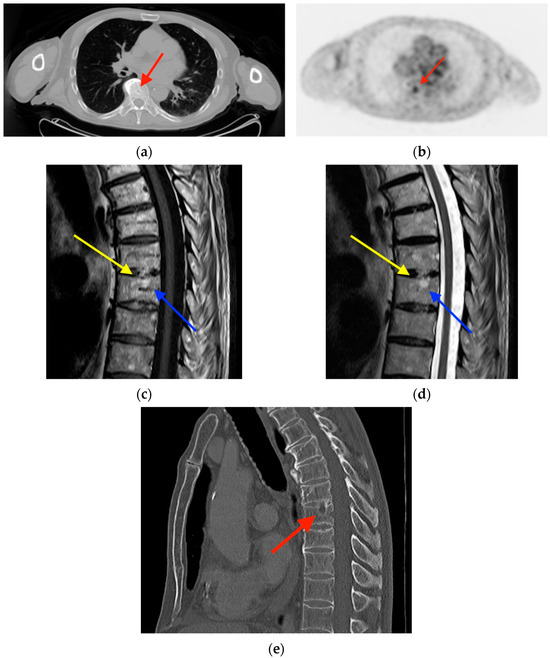

2.5. Vertebral Hemangioma